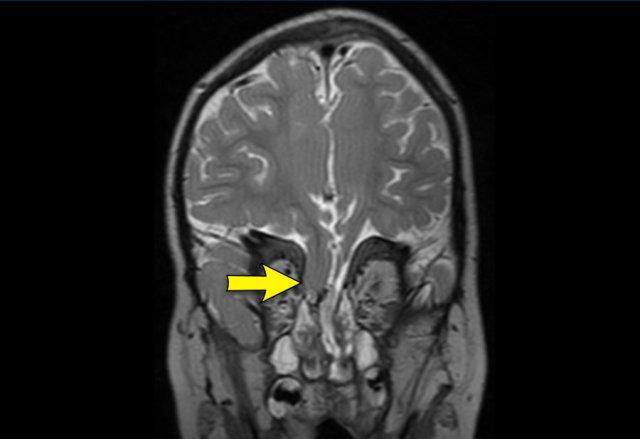

Typically, the entire side is pushed forward, hence the ear will be seen more anterior than on the contralateral side (arrow).

This is in contradiction to a posterior plagiocephaly resulting from a unilateral lambdoid suture stenosis, where the mastoid and the ear are pulled down and drawn back.

Positional plagiocephaly. The left ear is pushed forward.

Note: Adequate clinical evaluation and/or ultrasound should have obviated the need for CT.